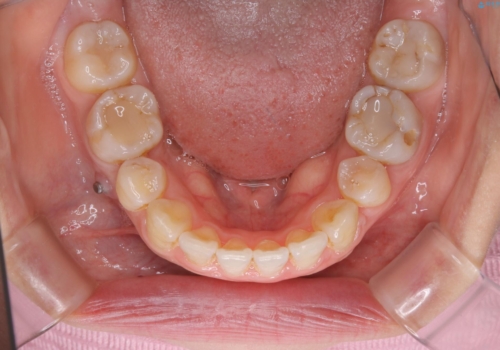

下の前歯にはかなり多くの歯石が付いており、デンタルフロスでもう少し防げるため、使用法や頻度を確認しました。

インビザラインの矯正治療は、マウスピースの使用時間が少ないとマウスピースと歯のフィッティングが悪くなりシュミレーション通りに歯が動かなくなるため、追加アライナーといって、再度スキャニングを行い新しいフィットの良いマウスピースに変えていきます。そのスキャニング時にアタッチメント(歯の表面に付いた突起)も除去するため、そのタイミングでクリーニングするのもおすすめです。